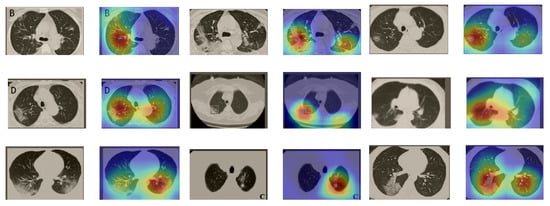

5.5.2. The Grad-CAM Visualization

In order to make our models more transparent and visually interpret the results, we provide the Grad-CAM localization maps generated by using different models. We utilized the CT images from COVID-19 class from the test set for each dataset, and highlight the important regions considered for the prediction. Figure 13 shows examples of CT images from the SARS-CoV-2 CT dataset and their localization maps. Interestingly, in most of the cases, our InceptionV3 model correctly classified them as COVID-19 cases and highlighted the regions of abnormalities in the CT scans, which are important for the model’s decision.

Figure 13.

Grad-CAM visualizations for examples of CT images from the SARS-CoV-2 dataset. Our InceptionV3 model correctly classified them as COVID-19 and localized the most relevant regions used for its decision. The first, third, and fifth columns show CT images with COVID-19 findings, whereas the second, fourth, and sixth columns represent their corresponding localization maps generated by Grad-CAM.